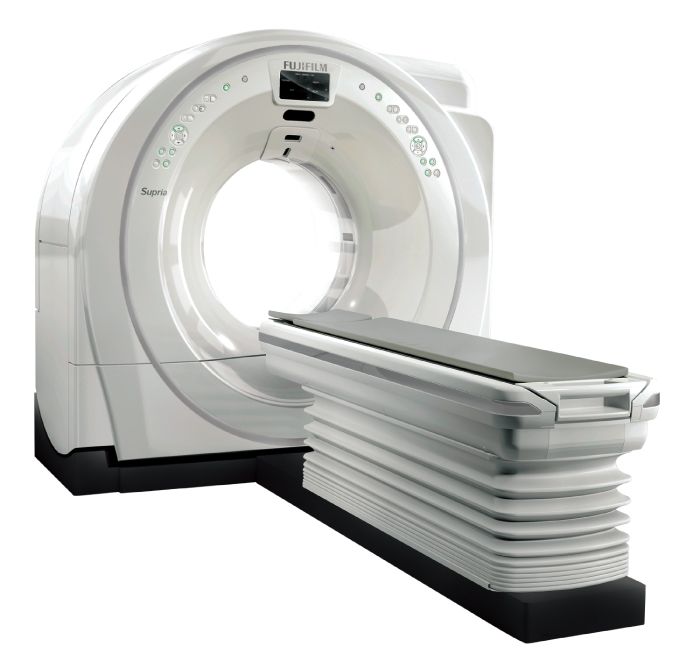

CT

AI技術を用いて開発した

画像処理システム搭載の

64列マルチスライスCT装置を導入

- 高精度画像

- AI技術を活用して設計したソフトウェアと0.625mm✕128枚のスライスから臓器の立体的な情報が得られます

- 検査時間の短縮

- 胸の検査は4~6秒ほどの息止めで撮影できます。

- 身体にやさしい

- AI技術を活用して開発した画像処理技術を搭載。

X線の被ばくを最大83%抑えられる、身体にやさしい検査が可能です。